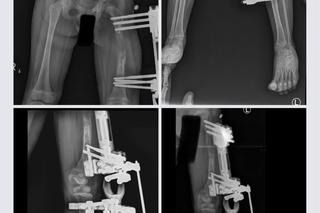

Zosia Szustakowska - to córeczka policjantów z wielkopolskiej i poznańskiej drogówki. Dziewczynka urodziła się z chorą, krótszą nóżką. Rodzice od razu postanowili zawalczyć o jej zdrowie. Dziewczynka przeszła trzy operacje wydłużenia nóżki. Pierwszą operację - biodra - była dwa lata temu. Kolejną operacją było wydłużenie kości udowej - noga Zosieńki została wydłużona prawie o 6 cm.

Potem odbyło się usunięcie aparatu zewnetrznego - mówi mama dziewczynki, Magda Szustakowska, która opisuje, że Zosia po zabiegach była na bardzo silnych lekach przeciwbólowych. Także każde ćwiczenie w czasie rehabilitacji związane było z ogromnym bólem. - Był krzyk i płacz, i trzeba było pilnować Zosi rączek, żeby nie wkładała ich do buzi, bo gryzła je do krwi - opowiada kobieta.

Chociaż wszystko wydawało się już być na dobrej drodze, 8 maja, w trakcie szpitalnej konsultacji okazało się, że jest potrzebny kolejny, pilny i bardzo kosztowny zabieg - osteotomia miednicy. Rodzice Zosi - Magda i Daniel muszą teraz uzbierać ogromną kwotę 120 tys. zł, aby Zosia mogła odzyskać sprawność!

Operację wykonuje polski zespół z kliniki Paley European Institute, a lekarzem prowadzącym Zosię jest nieoceniony doktor Tomasz Albrewczyński. Zosi można pomóc TUTAJ. Liczy się każda, nawet najdrobniejsza wpłata.